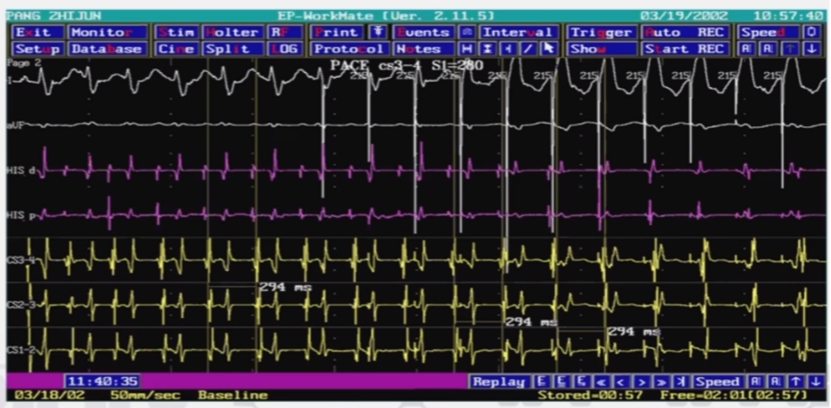

无冠窦房速 NCS AT

-

体表心电图P’波窄小,I、AVL导联 P波多直立,II、III、AVF导联P波呈负向或负正双向,V1、V2 导联P波负正双向或低平,V3-V6导联 P波的方向无一定规律。

最早激动在右心房希氏束区域,但在希氏束旁区域消融无效;激动标测显示无冠窦激动较右心房希氏束区域早,在无冠窦内放电消融可终止心动过速。

突发突止;易被心房程序刺激诱发和终止;心动过速发作时心室刺激对心动过速无影响;心动过速能被腺苷终止。

无冠窦房速心电图

体表心电图P’波窄小,I、AVL导联P波多直立,II、III、AVF导联P波呈负向或负正双向,V1、V2导联P波负正双向或低平,V3-V6导联P波的方向无一定规律。

无冠窦房速激动标测和消融